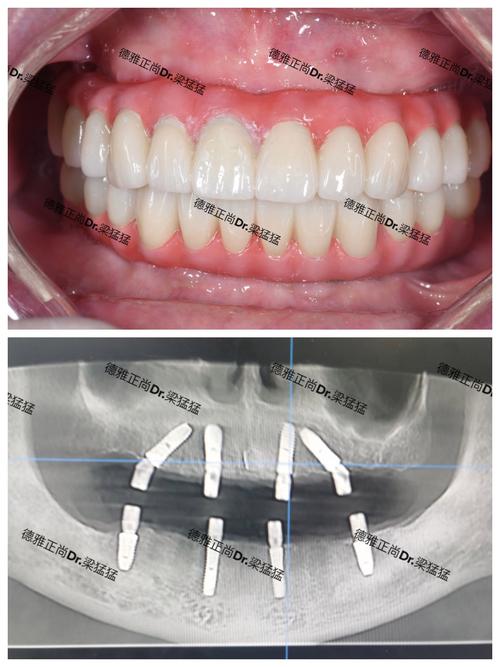

| 步骤 | 传统种植 | 即刻种植 |

|---|---|---|

| 拔牙 | 先拔牙,等待3-6个月愈合 | 拔牙后立即植入种植体 |

| 植入种植体 | 骨愈合后手术植入 | 拔牙同期植入 |

| 骨结合 | 3-6个月 | 可能缩短至1-3个月 |

| 戴牙冠 | 骨结合后安装最终牙冠 | 部分可当天戴临时牙冠 |